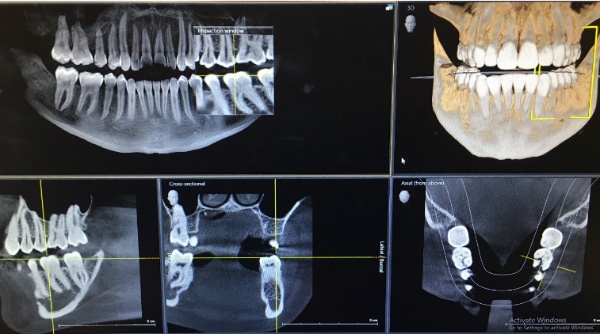

We use the most up to date equipment available, together with the most comfortable dental chair made.